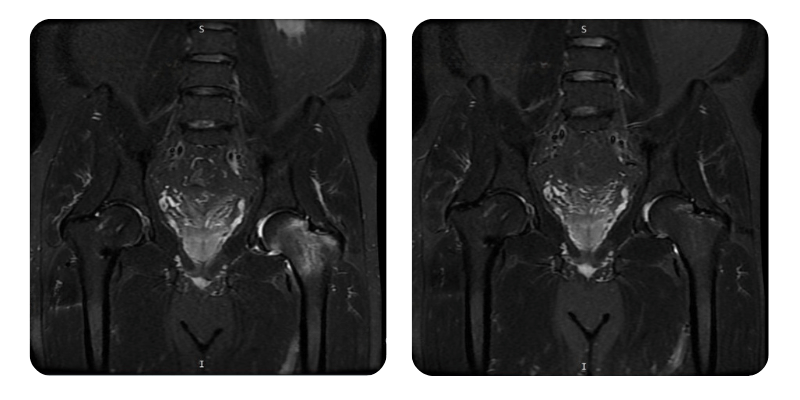

Before

After

B.A.M., 56 years old - Avascular necrosis of the left femoral head and neck, post right femoral neck fracture

Diagnosis: Avascular necrosis of the left femoral head and neck, post right femoral neck fracture.

Therapeutic interventions: 20 hyperbaric oxygen therapy sessions.

Evolution: After completing 20 hyperbaric therapy sessions, the patient shows an improvement of approximately 90%, with complete remission of lower back and hip symptoms. Mobility has significantly improved, with no nighttime pain and no need for additional interventions.